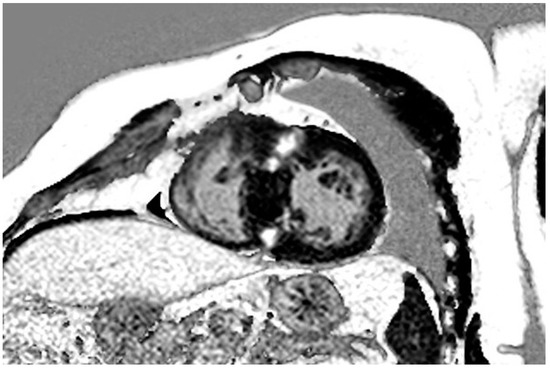

| Cardiovascular Magnetic Resonance Imaging | |||

| LGE (n) | 150 (78%) | 193 | |

| LGE size (g) | 4.7 (0.9–9.7) | 0–169.3 | 193 |

| LGE size (% of LV mass) | 3.7 (0.8–6.9) | 0–43.9 | 193 |